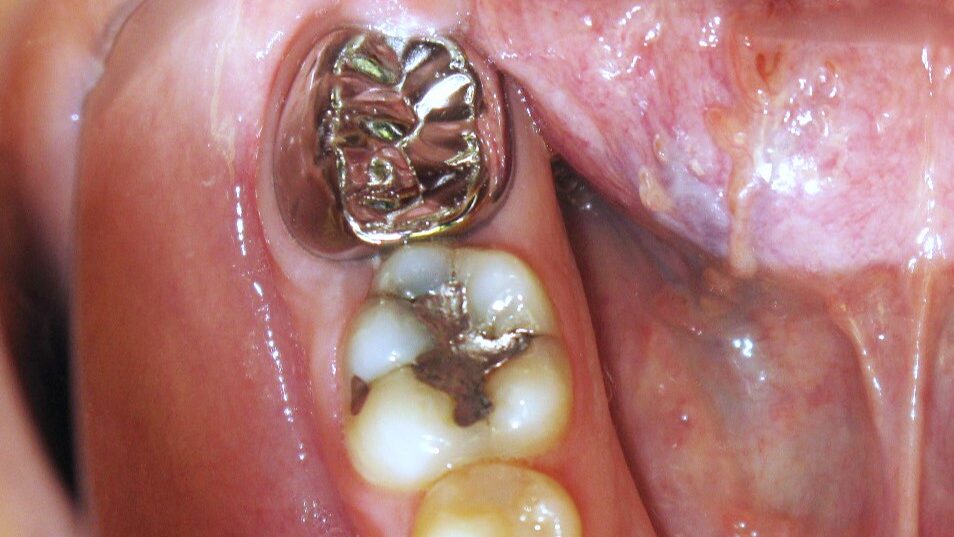

Green Teeth? The Many Shades of Congenital Syphilis

Figure2 alternate text for this image

It is a disease that you will learn about in dental school, but rarely see in actual practice. And given the many, varied features of congenital syphilis, when you do encounter your first case, you may need to review this condition and its presentation. Syphilis, generally, is on the rise in Canada. Between 2005 and … Read more